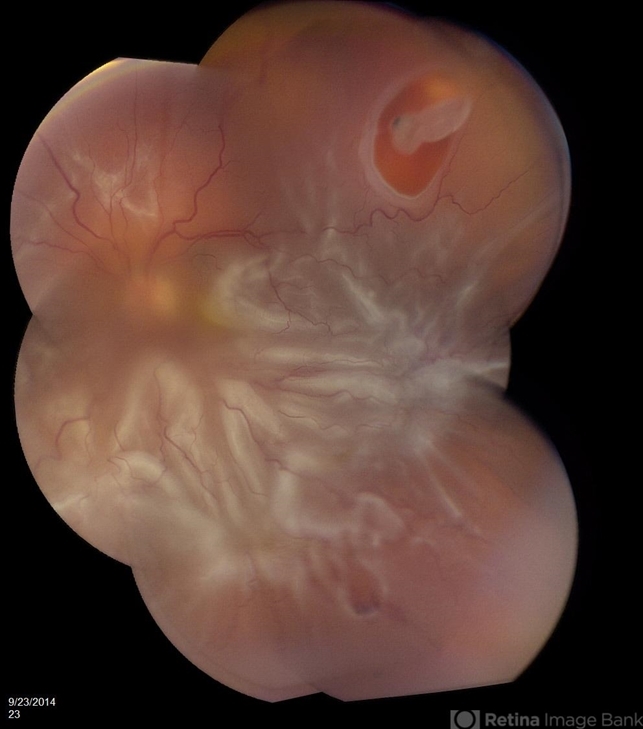

- proliferative vitreoretinopathy (PVR), retinal tear

- 63-year-old pseudophakic male with hand motion vision in the left eye due to a total retinal detachment with severe proliferative vitreoretinopathy.